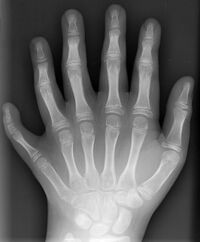

赤ちゃん 指6本 原因- 指が6本以上、『多指症』とは? 『多指症』 とは手足に生じる先天性の形状異常で手足の指が6本以上ある形状異常のことをいいます。 手の多指症に関しては、なんと胎児の 1,000に1~2人くらいの割合 だそうです。足指の場合は、その半分くらいだそうです。赤ちゃん 指6本 原因 5 Posted by Leave a comment on 赤ちゃん 指6本 原因 5

多指症、多趾症について 生まれつき手や足の指の数が6本以上ある状態 胎児の成長過程で、指が作られる時に、裂け目が入り6本目(以上)の指ができる 妊娠7週目あたりで胎児の指ができる時期に指が多く生じる 罹患率 は出生時00人あたり12人 男児にやや多い 手では親指に起こることが多い 足では小指に起こることが多い 赤ちゃんの歯磨き、いつからはじめる? 歯が生え始めるのは? 歯磨きを嫌がらないための事前準備 5~6ヶ月ごろから生え始める赤ちゃんの歯 赤ちゃんの歯磨き、まずは1日1回から、やり方は? 歯磨きの回数は、1日1回から 歯ブラシの選び方 歯の磨き

指が6本 多指症 の原因は 遺伝確率や合併症 手術後画像や有名人まで 女性のライフスタイルに関する情報メディア